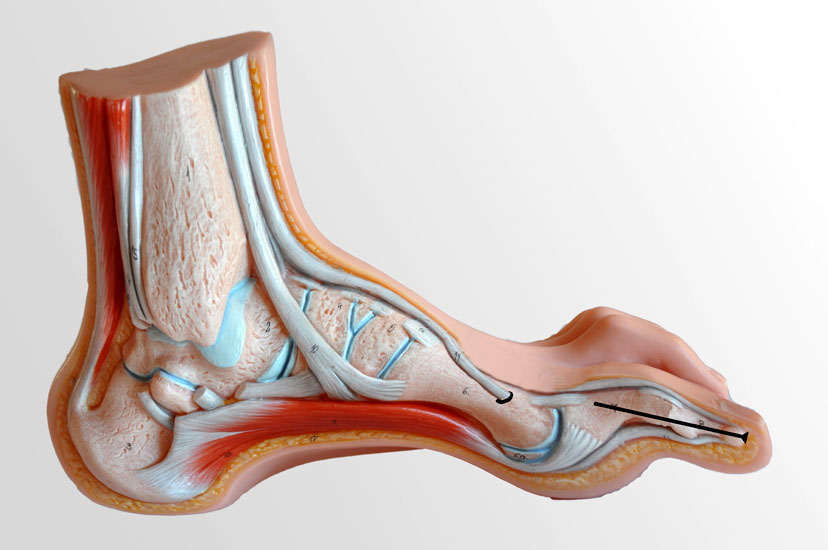

Lateralisierende Calcaneus-Osteotomie (Abb. 2 und 3, Video 2)

Die lateralisierende Calcaneus-Osteotomie ist ein Standard-Operationsschritt bei fast jeder Hohlfuβkorrektur. Der biomechanische Effekt der Osteotomie ist eine Verschiebung des Fersenkontaktpunktes und damit der beim Rückfuβ varus medialisierten Belastungsachse durch das OSG nach lateral. Diese statische Rückfuβ-Korrektur allein ist in der Lage, den bei Pes cavovarus anteromedial erhöhten OSG-Druck, der sehr wahrscheinlich zur korrespondierenden Arthrose führt, zu neutralisieren 7. Zuklappende Osteotomien mit Entnahme eines lateralen Knochenkeils haben sich dabei weniger effektiv gezeigt als solche mit Lateralisation des Tubers. Mit der Lateralisation des Achilles-Ansatzes verringert sich die Inversionskraft der Sehne zugunsten der schwachen Eversion, wodurch gleichzeitig die Prädisposition für Supinationstraumata reduziert wird. Neben der klassischen Dwyer-Osteotomie (Entnahme eines lateralen, vertikalen Keils 8 haben sich vor allem die technisch einfache Verschiebe-Osteotomien („sliding osteotomy“) und die Z-förmigen Osteotomien (Pisani 1993, Malerba 9) mit Entnahme eines lateralen Keils aus dem horizontalen Anteil der Osteotomie aber ohne Lateralisation des Tuberfragmentes, sowie die Korrektur nach Hintermann (Knupp 2008) mit zusätzlicher Lateralisation des Tuberfragmentes) durchgesetzt. Bei neutral aligniertem OSG ist keine supramalleoläre Tibia-Osteotomie zur Korrektur des Rückfuβ varus indiziert. Generell sollten Osteotomien gegenüber korrigierenden Arthrodesen der Vorzug gegeben werden. Die im Folgenden beschriebene Verschiebeosteotomie ist technisch einfach und hinsichtlich OSG-Druckneutralisation ebenso effektiv wie die Z-Osteotomien 7.

• Umfahren des Calcaneus mit Hohmann Hebeln und Markieren der Osteotomie mit 2 1.6 Kirschnerdrähten; Kontrolle der korrekten Osteotomie-Ebene im BV, diese sollten, da in der Regel keine Verkürzung oder Verlängerung des Rückfuβes gewünscht ist, in der axialen Projektion genau rechtwinklig zur Achse des Calcaneus verlaufen; seitlich beginnt die Osteotomie proximal etwa 2 cm anterior des Achilles-Ansatzes und läuft etwas schräg nach distal-anterior.

• Häufig verschiebt sich das Tuber-Fragments bei der Korrektur etwas nach proximal, was aber bei steilem Calcaneus (hoher “calcaneal-pitch” Winkel) erwünscht sein kann.

• Kontrolle der korrekten Schraubenlage im BV (Abb. 3).